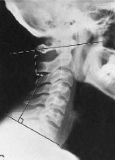

Q what is the name of this measurement? and what is the average + range?

A: Atlantodental Interspace (ADI)

assesses the integrity of the transverse ligament. Average and range for Adults: 1-3 mm. Average and range for Children: 1-5 mm